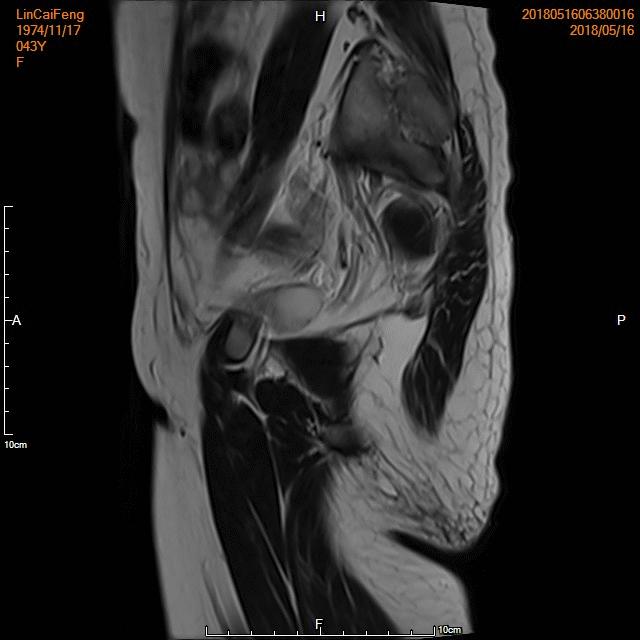

例3

中年患者,发现“子宫腺肌症”10年余,近5年痛经、月经量增多等症状明显加重,导致贫血,严重影响生活质量。

- 术前彩超、磁共振检查显示子宫明显增大,子宫前壁可见弥漫型子宫腺肌症病灶,合并粘膜下、肌壁间子宫肌瘤。

横断位

冠状位

矢状位